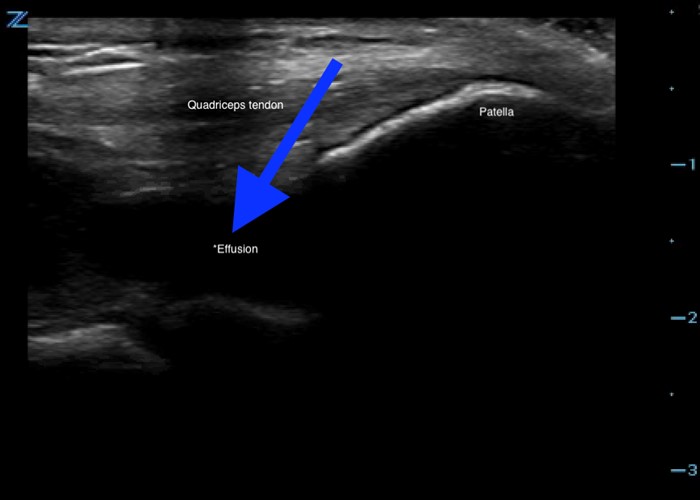

Using the high-frequency linear probe, typical views are obtained superior and inferior to the patella, as well as medial, lateral, and posterior to the knee joint. Views superior and inferior to patella assess for the integrity of the quadriceps and patellar tendons, the patella, as well as presence of knee effusion. Normal examination of the overlying skin and absence of cobblestoning of the soft tissue on ultrasound lessens the likelihood of cellulitis and abscess. Figure 1 shows the anterior ultrasound view of the knee, the patella. An intact patella should demonstrate the uninterrupted hyperechoic curvature of the cortical surface. In figure 1, we see an unmistakable cortical disruption (between the two red arrows), indicating a patellar fracture. Knee effusions will appear as an anechoic collection, indicated by the blue arrow, deep to the tendons. (Fig. 2) Medial and lateral views can also demonstrate effusions. Complex effusions such as hemarthrosis appear as hypoechoic collections if clotting has occurred. Figure 3 demonstrates a traumatic hemarthrosis identified by the green arrow. Figure 4 shows another simple knee effusion, indicated by the green arrow, without a history of trauma. Aspiration in the emergency department or office can be useful in directing therapy. In Figure 4, we see the needle approaching the effusion from the left side of the screen highlighted by the red arrow. Lastly, the posterior aspect of the knee contains the popliteal vessels. The popliteal vessels should be identified by Color Doppler, allowing differentiation from the non-vascular structures. Figure 5 shows a cystic non-compressible, anechoic structure without internal echoes within the popliteal fossa highlighted by the yellow arrow.

Figure 2